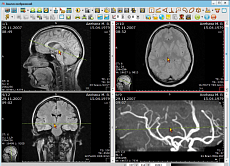

Радиологическая информационная система

Радиологическая информационная системаPACS/RIS АПК АрхиМед

- Мультипланарная реконструкция (MPR) выбранной серии изображений

- Экспорт изображений на удаленный DICOM сервер

- Телемедицинские консультации

- Формирования протоколов исследований